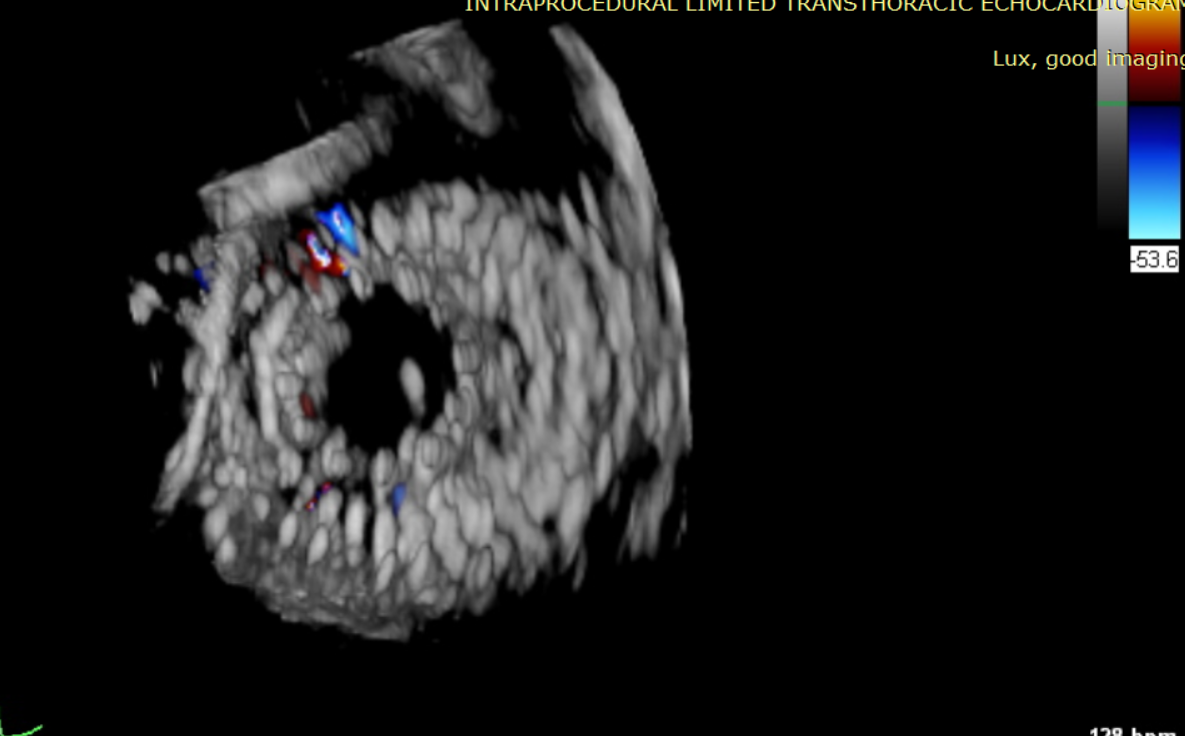

術(shù)后超聲提示僅殘余輕微瓣周漏